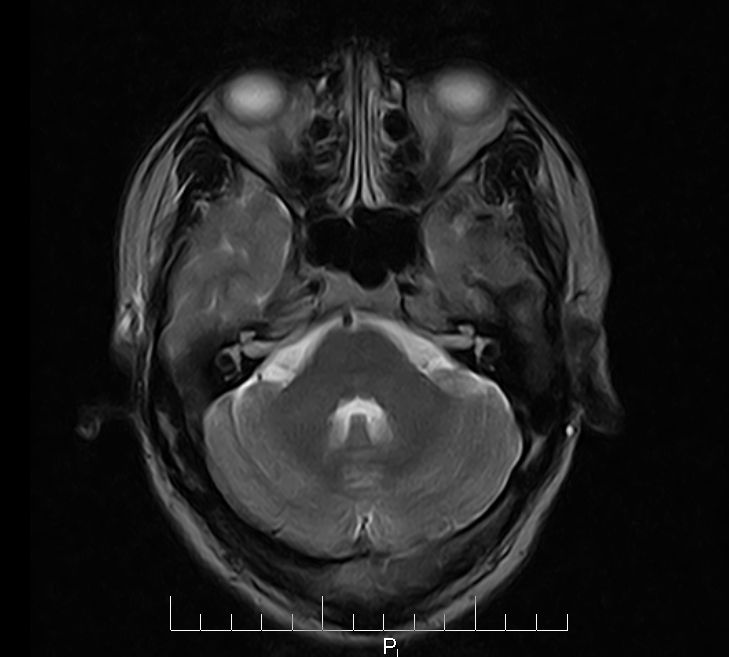

标题: MRI2379:30岁,男,癫痫10年,请各位看一下;CT示:左颞叶钙 [打印本页]

标题: MRI2379:30岁,男,癫痫10年,请各位看一下;CT示:左颞叶钙

左颞叶区见不规则点状混杂信号影

考虑血管畸形

支持2楼 左颞叶区见不规则点状混杂信号影,考虑动静脉畸形。

考虑左侧颞叶脑血管畸形(avm)。

考虑左侧颞叶脑血管畸形(avm)。----t1低等高混杂信号,t2等高信号周边较多流空血管影[冠状位明显],mra左侧大脑中动脉受压,远侧聚集.